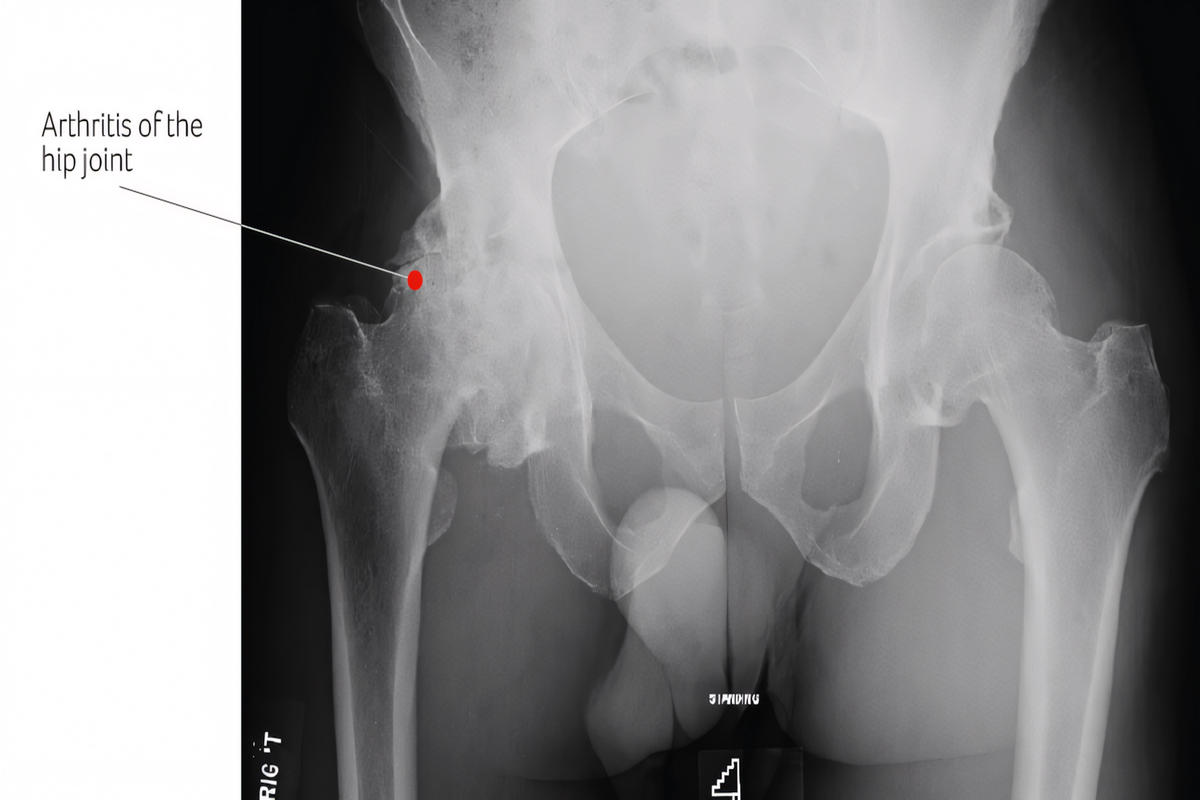

Ακτινογραφία ισχίου αποτελεί την εξέταση πρώτης γραμμής και αναδεικνύει:

Στένωση μεσάρθριου διαστήματος

Οστεόφυτα

Υποχόνδρια σκλήρυνση

Παραμόρφωση κεφαλής

Η μαγνητική τομογραφία (MRI) χρησιμοποιείται σε πρώιμα στάδια ή σε υποψία οστεονέκρωσης. Η αξονική τομογραφία (CT) βοηθά σε σύνθετες μετατραυματικές περιπτώσεις.